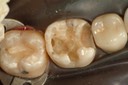

Gary Umeda #30 - 31 pre-op